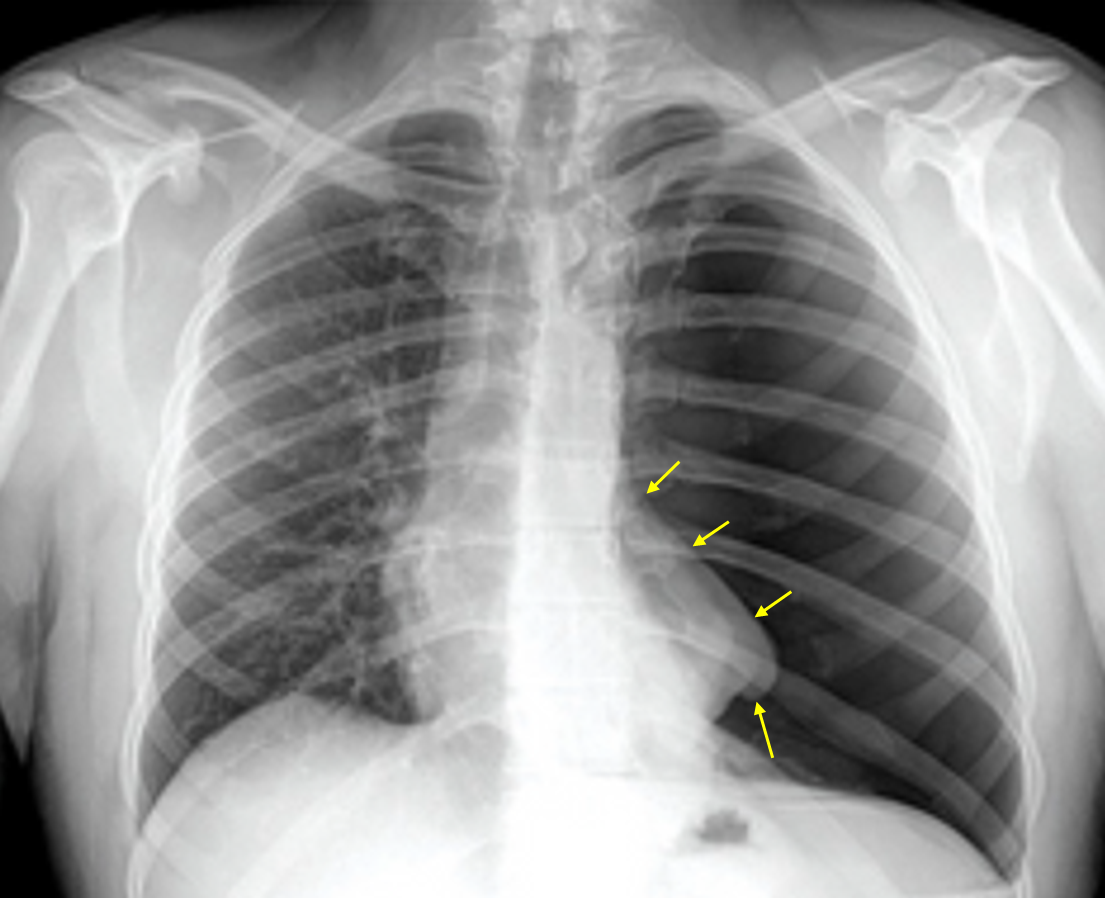

68세 남자가 3시간 전부터 숨이 차다며 병원에 왔다. 가슴이 아프고 점점 숨쉬기가 힘들어 진다고 한다. 20년 전부터 혈압 강하제를 복용하고 있다. 40갑·년 흡연자이다. 혈압 90/52mmHg, 맥박 112회/분, 호흡 26회/분, 체온 36.8℃이다. 가슴 청진에서 심음은 정상이고 왼쪽 가슴에서 호흡음이 들리지 않는다. 양쪽 정강뼈 앞 오목부종은 없다. 가슴 X선 사진이다. 혈액검사 결과는 다음과 같다. 가능성이 큰 진단을 고르시오 (한 가지).

Img | CXR : 좌측 폐 bronchovascular marking 사라짐, 심장 우측 이동 |

Unstable V/S와 large mediastinal shift가 관찰되므로 tension pneumothorax를 진단할 수 있다.

• CXR에서 좌측 폐의 폐혈관 음영이 완전히 사라졌고, 심장과 기도가 우측으로 이동한 소견으로 보아 긴장성 기흉이 의심된다.

• 저혈압, 빈맥, 호흡수 증가 소견 또한 긴장성 기흉에 의해 정맥환류 감소로 인한 순환부전과 호흡부전에 의한 것으로 생각할 수 있다.